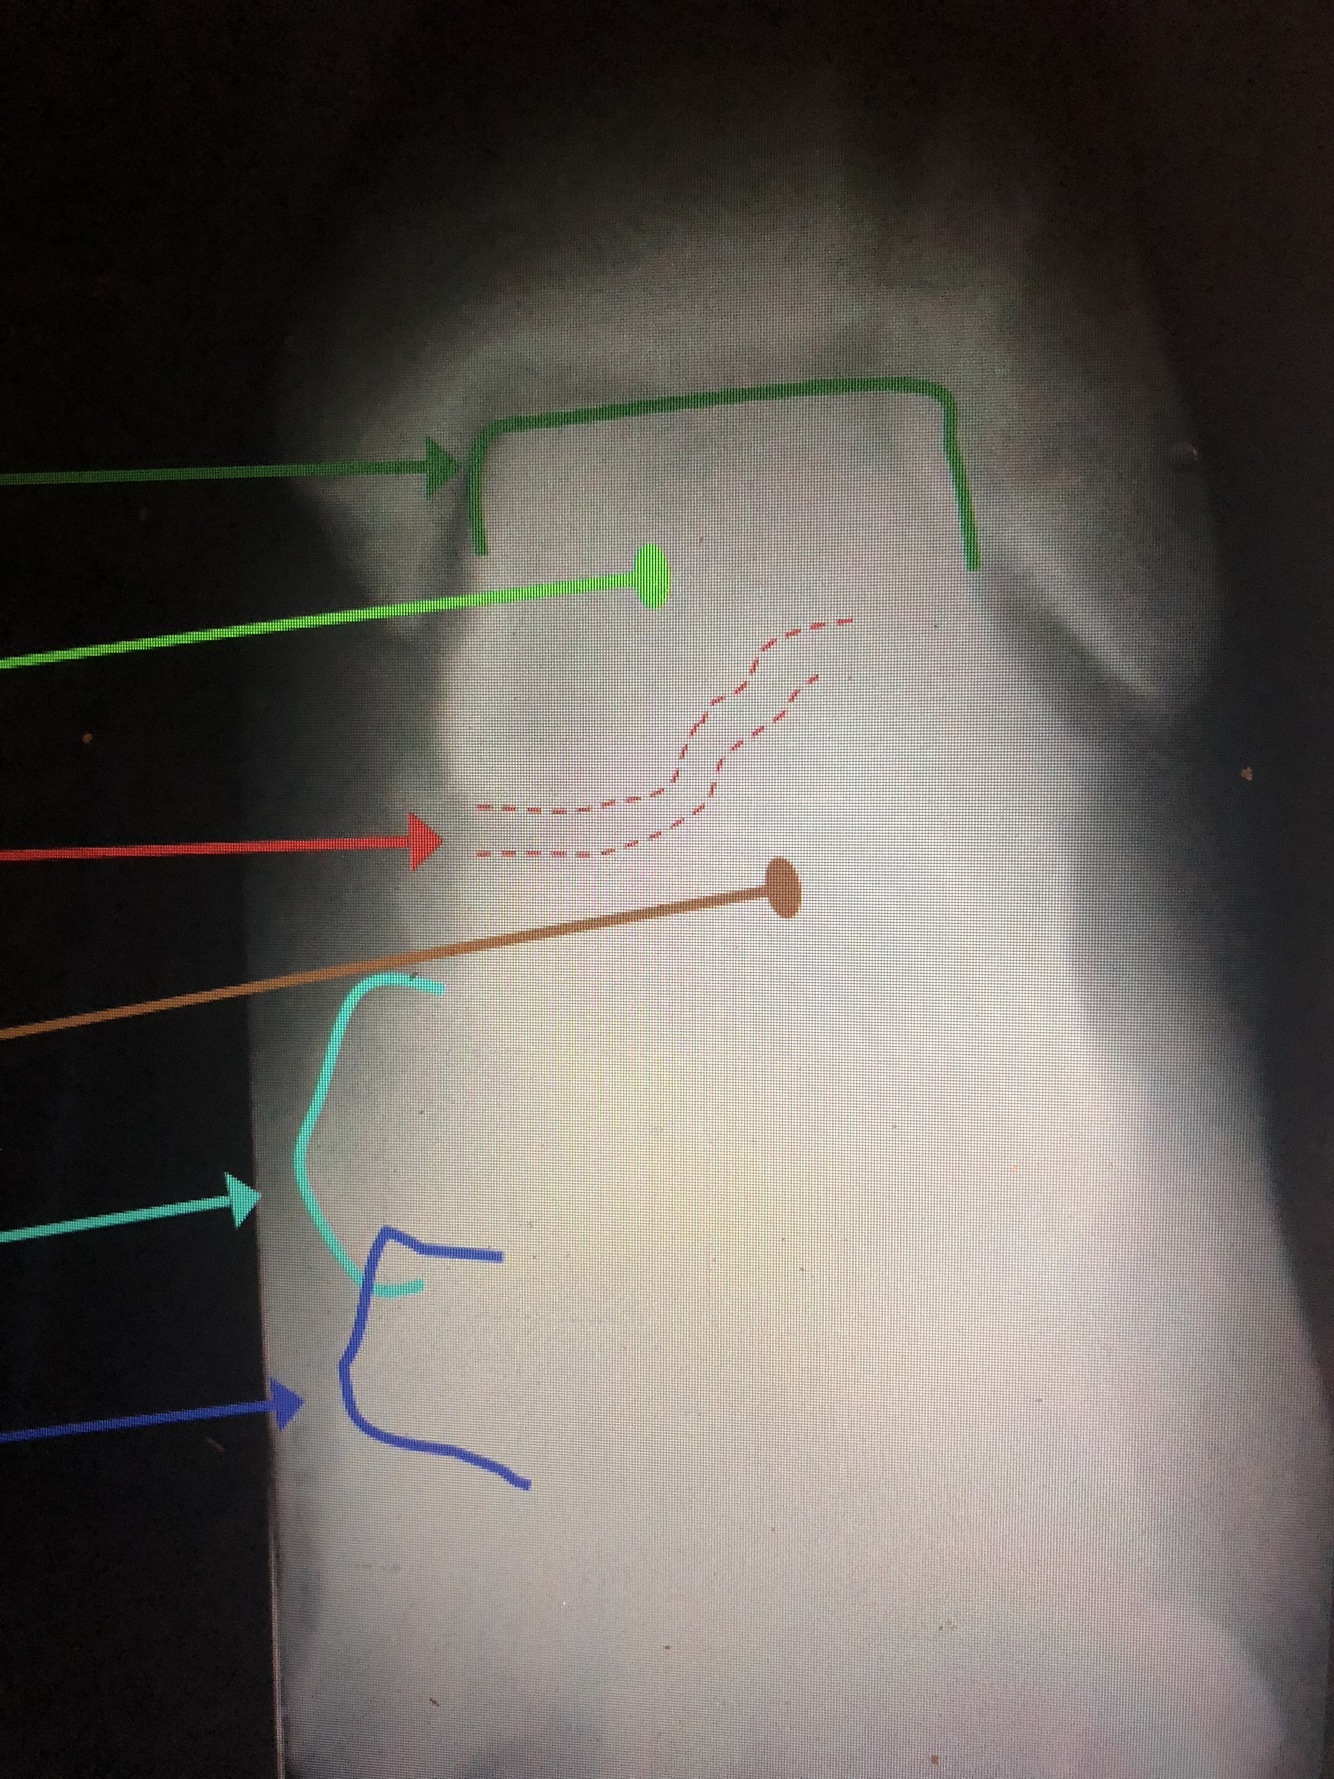

What bone is yellow?

Talus

What bone is brown?

Navicular

What bone is light green?

Calcaneus

What bone is light blue?

Cuboid

What is the yellow dotted line?

Fibular Notch

What is the dark blue line?

Plafond

What is the red line?

Posterior Malleolus

What is the light blue line?

Medial Malleolus

What is the blue line?

Lateral Malleolus